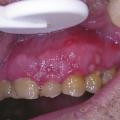

La primo-infection herpétique se traduit par une gingivostomatite aiguë survenant souvent pendant la petite enfance, mais elle n’est pas rare chez l’adolescent ou l’adulte jeune. Elle débute par de la fièvre, un malaise général, des douleurs pharyngées et gingivales ; des vésicules multiples parfois confluentes et polycycliques apparaissent sur une muqueuse érythémateuse. L’atteinte gingivale est constante (fig. 5 ) associée à des adénopathies cervicales sensibles. La guérison est spontanée en 2 à 3 semaines. L’herpès récurrent, dû à la réactivation du virus resté latent après la primo-infection, est souvent labial, classique « bouton de fièvre », précédé par une sensation de cuisson ou de prurit ; des vésicules groupées en bouquet se forment rapidement sur une zone érythémateuse, se rompent puis sèchent, formant une croûte jaunâtre. La fréquence est variable, favorisée par certains facteurs : stress, fièvre, cycles menstruels, traumatisme, exposition solaire… D’autres localisations bucco-faciales sont possibles telles que le seuil narinaire et les joues, la fréquence de la localisation intra-buccale est sous-estimée : gencives, palais (fig. 6 ). Le zona buccofacial est lié à la résurgence du virus varicelle-zona resté à l’état latent au niveau des ganglions sensitifs des nerfs crâniens (zona du nerf trijumeau) après la primo-infection varicelleuse. Il est plus fréquent chez les patients immunodéprimés. L’éruption, parfois précédée d’un syndrome infectieux modéré et de douleurs de topographie radiculaire, est vésiculeuse et intéresse le territoire d’un ou de deux troncs du nerf trijumeau. Le zona de la branche ophtalmique du trijumeau met en jeu le pronostic fonctionnel visuel.